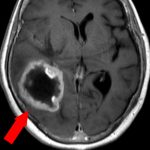

360

'22年12月

70代

右前頭葉膠芽腫

頭蓋内腫瘍摘出術

No.’22_117 手術前1

No.’22_117 手術前2